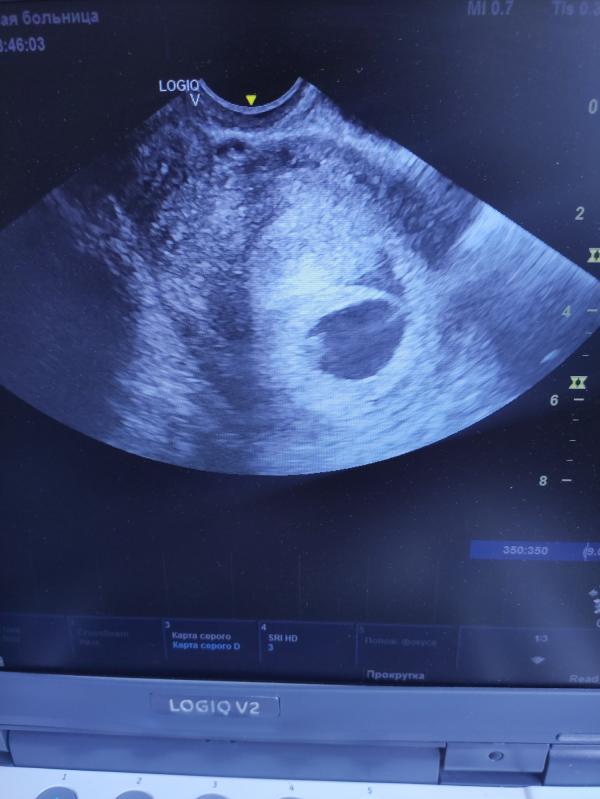

Добрый вечер. Хотя не такой уж он и добрый. Завтра к гинекологу. Была на узи, образовалась гематома 🤦🏽♀️🤦🏽♀️🤦🏽♀️, по ходу надо в больницу ложиться 😔

У Вас очень маленькая гемотома) просто старайтесь больше лежать, у меня сама рассосалась.